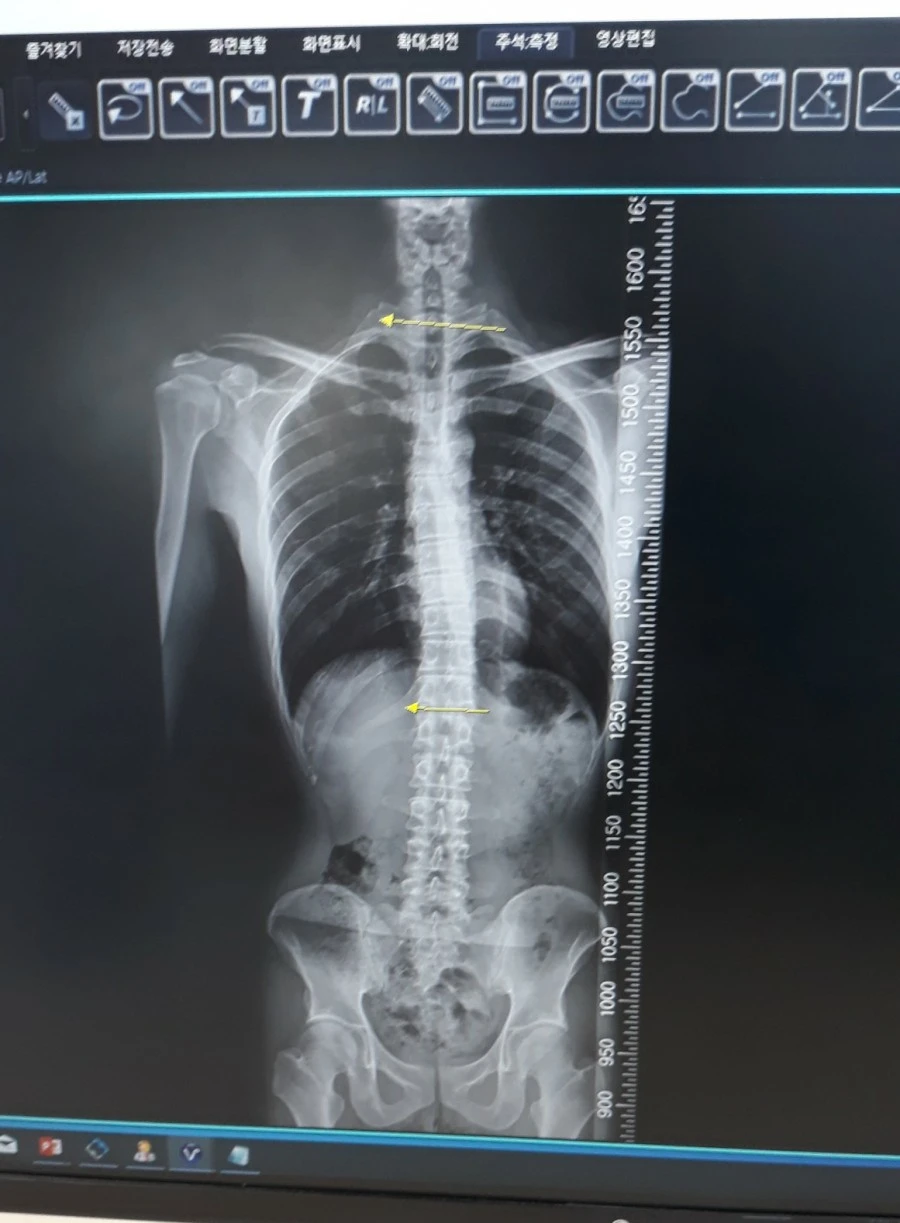

1574507740842.jpg?type=w1 척추 엑스레이 사진

평소 20분 정도 서있거나 걸으면 허리가 아파와 혹 디스크나 다른 허리질환이 있는 건 아닐까 걱정이 많았다. 증상을 설명하니 의사 선생님은 척추관 협착증을 의심하셨다. MRI와 CT로 병변 확인이 가능하다길래 정확한 진단을 위해 MRI 촬영을 했다.

검사 결과 약간 척추가 휘고 어깨 높낮이가 다른 것을 빼면, 허리는 건강하단다. 50만원이나 되는 거금을 들였지만 건강하다는 말에 안심이 되었다. 근데 저 정도의 척추 휨 현상은 통증을 유발하지 않고, 교정도 불필요하다고 하신다. 별로 믿음은 가지 않았다.

반면 어깨는 엑스레이상에서 하얀색 병변이 발견되었다. 회전근개파열은 아니고 염증인 것 같다며 어깨에 무리가 가는 운동(푸시업이나 풀업)은 피하라고 하셨다. 그리고 물리치료를 권하길래, 체외충격파 치료를 받았다. 예상치 못했는데 엄청 아프다.